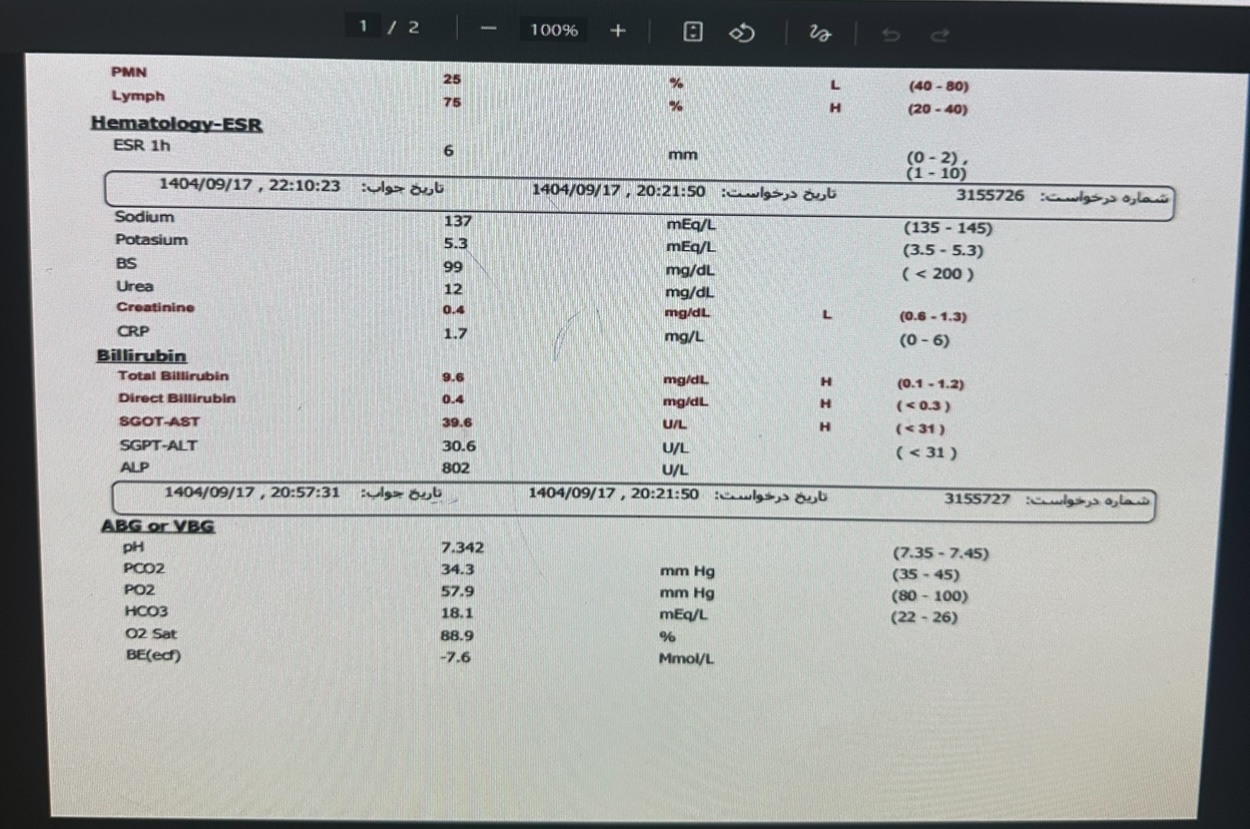

تو ازمایشات لنفوسیتوز

WBC=21000, lymph=78%

EsR,CRP=normal